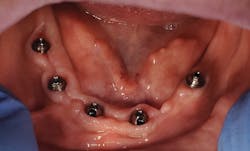

Multiunit abutments, such as those from BioHorizons, have a 45-degree conical connection (figure 1) that features a self- centering 22.5-degree angulation correction to help ensure a passive prosthetic fit and restorative flexibility to divergent implants. The multiunit abutment also provides the greatest range of angulation correction in both 17- and 30-degree offsets (figure 2). The placement of the multiunit abutments at the time of implant placement also allows for an impression process that is supragingival, which leads to less movement through the tissue, less discomfort for the patient, and quicker impression appointments.